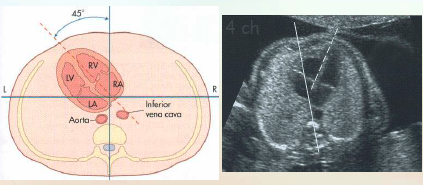

Transverse of 4 chamber heart

On transverse 4 chamber heart note the heart

Size: 1/3rd the size of the thorax

Axis: Between 40-45 degrees from the midline

*Should NOT be greater than 45 degrees

Position in thorax: Ventricles pointing toward the left

Surrounding fetal anatomy

what anatomy does the tran 4-chamber view demonstrate?

Both ventricles

Interventricular septum

Both atria

Atrial septum

Foramen ovale

Papillary muscles

Great vessels

Pulmonary artery

Aorta

Atrioventricular valves

Make sure they both open during diastole & close during systole (Right side is Tricuspid valve, Left side is Mitral valve)

Left atrium lies closest to the fetal spine

Four chambers should be nearly equal in size

Right ventricular apex may appear thicker due to the presence of the moderator band

Foramen ovale flap into left atrium